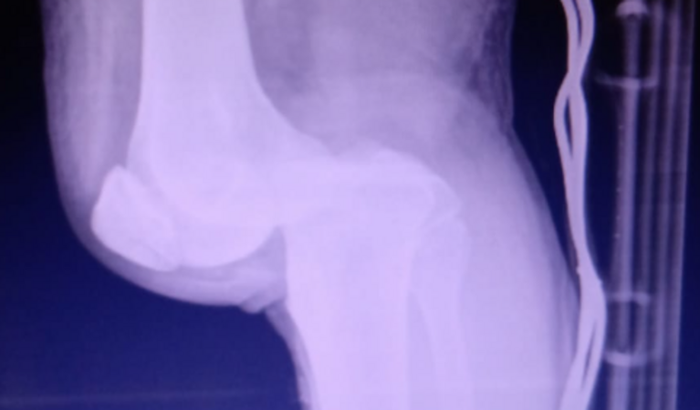

Eu sou o Deomar Werlang, sofri um acidente de trânsito no dia 22/01, o qual rompeu os tendões da minha perna, e me impossibilita de caminhar!